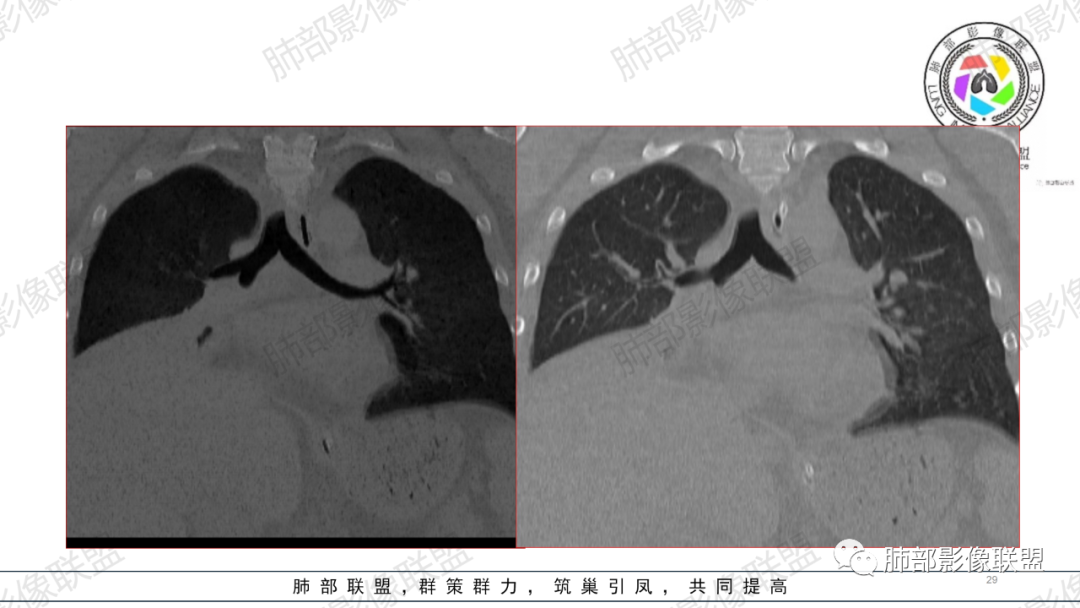

支气管痰栓或粘液阻塞,临床上并不少见,本例患者有腹部手术或胸部外伤肋骨骨折病史,其原因多是长时间采取一种被动体位,因怕疼痛而不敢咳嗽导致痰液引流不畅,自主排痰有一定的困难,导致痰液形成后不能及时排除。滞留痰液集聚形成痰块,混合坏死组织,部分形成痰栓。痰栓附着在气道壁上,局部气道变窄,如果不及时通畅气道,导致原来肺部、胸腔病变加重或出现新的病变,严重者可致局部气道闭塞,相应的肺叶出现肺不张CT上支气管粘液栓形态多样,可呈圆形,类圆形,条状、指套状、葡萄串状等。